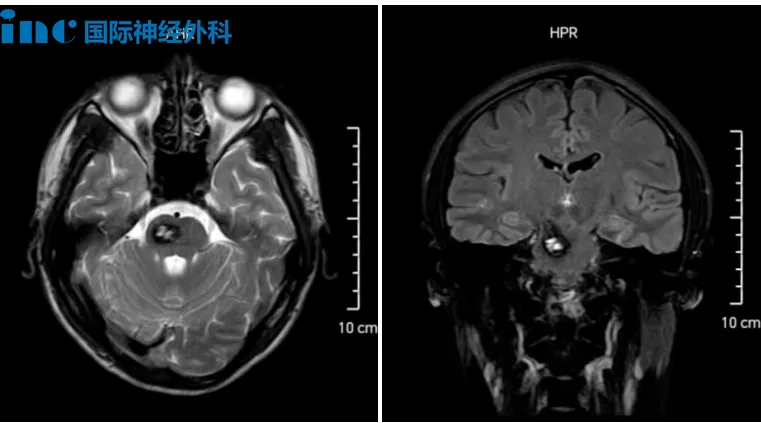

8歲的小航,同樣因外傷發(fā)現(xiàn)腦瘤,影像顯示其右側(cè)丘腦存在巨大腫瘤并伴隨腦積水。腫瘤位置深、體積大,每一步治療都如履薄冰,成為全家心頭沉甸甸的石頭。

它悄然潛入8歲小航的大腦,盤踞在右側(cè)丘腦與基底節(jié)區(qū)。初次發(fā)現(xiàn)時,腫瘤已顯露出不容小覷的規(guī)模——病灶大小約4.0cm×4.7cm×4.8cm,高度懷疑為彌漫中線膠質(zhì)瘤,并引發(fā)了梗阻性腦積水。在這幼小的頭顱中,腫瘤開始悄然作惡:小航出現(xiàn)記憶力減退、注意力難以集中,甚至喝水時嗆咳。

影像

面對面交流時,男孩的父母聲音里滿是憂慮:“這個腫瘤……是惡性的可能性大嗎?巴教授,您能為他手術(shù)嗎?”他們不曾想到,這顆隱匿的腫瘤竟已悄然壯大,成為全家心頭沉甸甸的巨石。

巴教授在詳細(xì)評估后,給出了明確而堅定的判斷:孩子有明確手術(shù)指征,應(yīng)盡快手術(shù),不能再拖延。而對于這個膠質(zhì)瘤,巴教授表示可能是低級別膠質(zhì)瘤,但還是要看最終手術(shù)病理。“